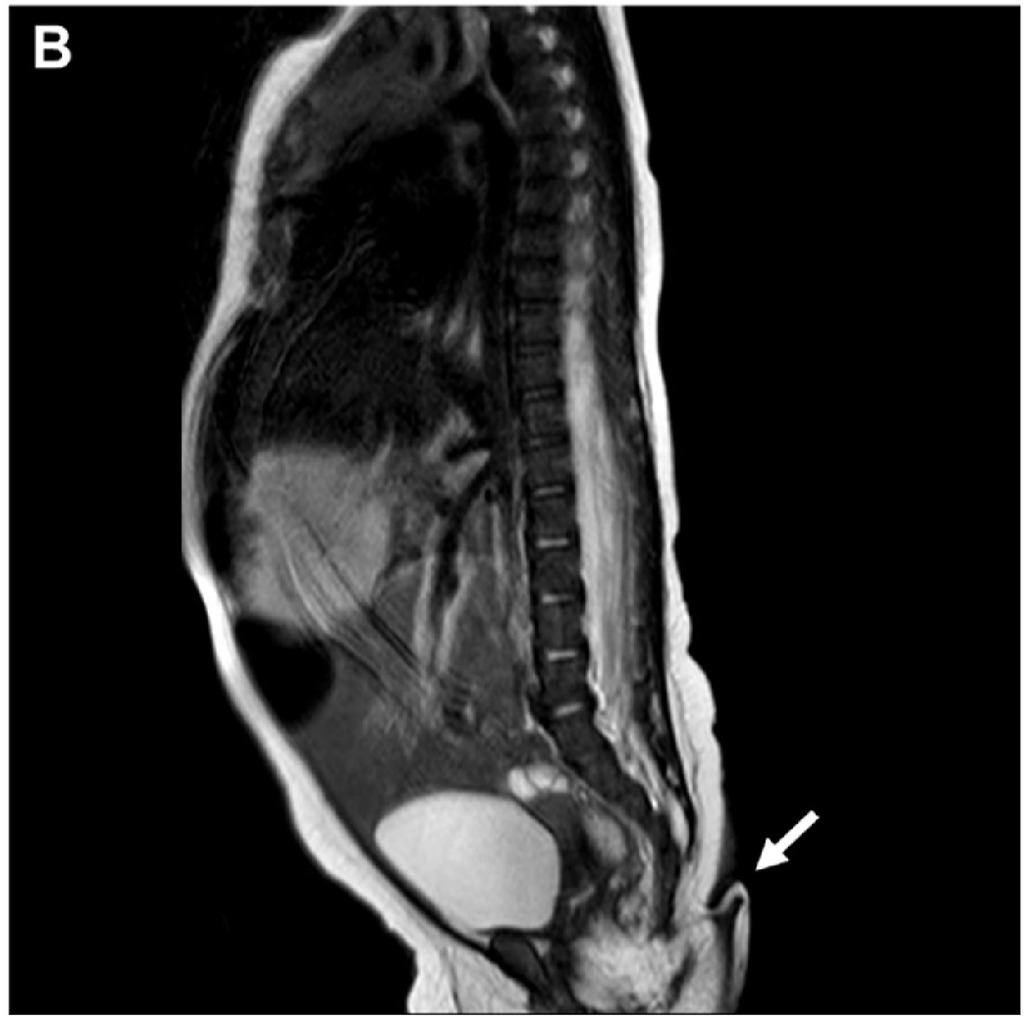

女嬰在2個月大時再度接受健康檢查,她的「尾巴」長度竟再增長0.8厘米。醫生判定她的體重成長符合標準,同時確認她的「尾巴」沒對身體造成負面影響。在排除所有影響生命的因素後,醫生團隊決定為女嬰動手術切除尾巴。慶幸最後手術順利完成,女嬰隨後沒有出現任何併發症狀,傷口亦順利修復重建。

過去亦曾發生BB出生時身體附帶尾巴事件。早前廣東東莞亦有一個初生嬰兒,屁股也長了一條小尾巴,5個月大的時候,父母發現兒子的下肢漸漸變得無力,求醫檢查後發現男嬰的尾巴連著的椎管內,竟有巨大的脂肪瘤壓迫着脊髓圓錐,幸手術切除後已無大礙。